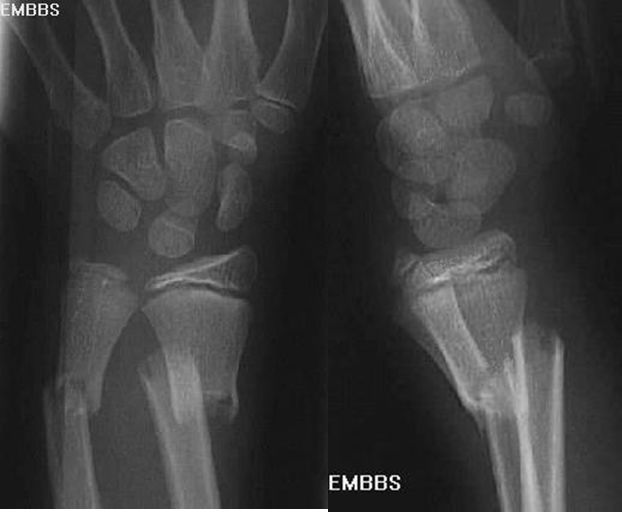

Colles骨折

• 桡骨远端骨折

• 骨折向掌侧成角

• 远折端向背侧移位

疼痛科怎么理疗疼痛科医生、康复理疗科医生、针刀针灸医生应掌握的常见骨科疾病X光片_https://www.jmylbn.com_新闻资讯_第21张

Smith骨折

疼痛科怎么理疗疼痛科医生、康复理疗科医生、针刀针灸医生应掌握的常见骨科疾病X光片_https://www.jmylbn.com_新闻资讯_第22张

正常腕关节